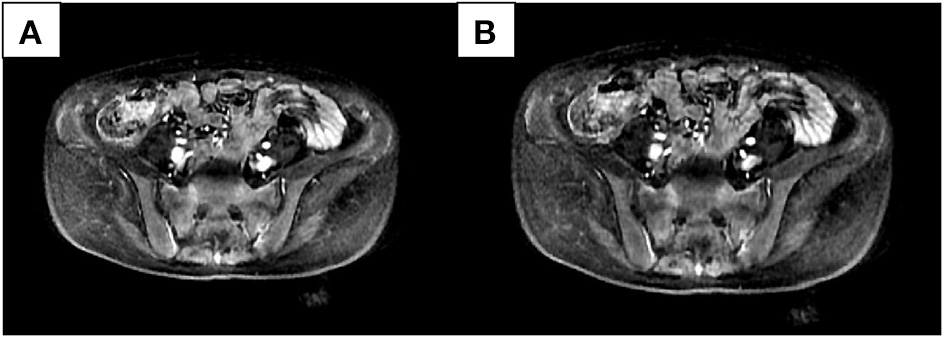

We compared patients with SIJ–MRI abnormalities between the two groups (10 in the osteomalacia group, and 18 in the SpA/AS group). In the osteomalacia group, seven patients met the definition for positive SIJ–MRI according to 2009 ASAS criteria (Figure 1), showing bilateral sacral involvement, and three (3/7) showed bone erosion. There was no significant difference in bone marrow edema (BME) signal score in SIJ–MRI between the two groups. However, bone erosion score was lower in the osteomalacia than the SpA/AS group (P < 0.05; Table 4).

Figure 1

Female, 28 years old, chief complaint of lumbago for 21 months, exacerbation accompanied by generalized asthenia for 6 months. Erythrocyte sedimentation rate, C-reactive protein, and human leukocyte antigen-B27 were all negative. Alkaline phosphatase was 269.6 U/L; inorganic phosphorus was 0.43 mmol/L. Bilateral sacral bone marrow edema signals could be seen in two continuous layers (A,B) in the short-tau inversion recovery sequence.